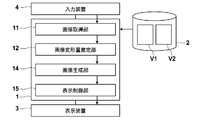

- the image acquisition unit 11 acquires the first image V1 and the second image V2 from the storage 2 to the memory.

- the image processing apparatus 1 detects that a predetermined alignment function is selected in the selection menu, the image processing apparatus 1 prompts the user to select or input information necessary for specifying the first and second images. Then, when the first and second images are specified by the user's operation of the input device 4, the image acquisition unit 11 acquires the first image V1 and the second image V2 from the storage 2 to the memory.

- the image generation unit 14 generates an image V1A obtained by converting the first image V1 using the conversion function determined by the image deformation amount estimation unit 12.

- FIG. 2 is a flowchart illustrating a processing flow of the image processing apparatus according to the second embodiment. The processing flow will be described with reference to FIG. First, the image acquisition unit 11 acquires a first image (first image data) V1 and a second image (second image data) V2 obtained by imaging a subject (S01).

- the image generation unit 14 converts and reconstructs the first image using the determined conversion function, and generates the image V1A (S08). Then, the display control unit 15 displays the generated image V1A and the second image V2 side by side so that they can be compared (S09).

- FIG. 5 is a schematic diagram showing a functional block diagram of the second embodiment.